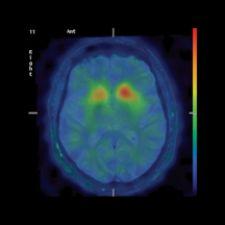

In the last few years, fusion imaging has enabled tremendous clinical milestones, such as using PET images on patients with Alzheimer’s disease to highlight any area of the brain with high concentrations of plaques. Another technique involves ictal-interictal image abstraction overlaid on MRI to identify abnormal bloodflow in the brain due to epilepsy and for epileptic surgery. For biopsy or surgery, fusing images of PET or SPECT on MRI or CT helps localize disease and anatomically guide the surgeon, and multitrace image fusion facilitates the treatment of patients with Hodgkin’s lymphoma.

“Multimodality image fusion in the brain is relatively easy, because the organ is relatively rigid. Automatic image registration and fusion of SPECT, PET and MRI is usually very rapid and effective,” explained S. Ted Treves, M.D., chief, Division of Nuclear Medicine, vice chairman for Information Systems, department of Radiology, Children’s Hospital, professor of Radiology, Harvard Medical School. “Image fusion in the body is not as easy as in the brain as the position of the body may not be the same during the acquisition of each modality. Also, the organs within the body are nonrigid (respiratory motion, cardiac motion, etc.), making exact image registration and fusion more difficult. These limitations can be sometimes overcome by using morphing methods or manual overrides.”

Another region of difficulty in visualization is with 2-D X-ray projection data for cardiology applications. Perfusion defects that are defined by SPECT or PET could be matched with the location of stenosis obtained by coronary CT angiography, but due to limitations of registration of 2-D X-ray projection data with perfusion data, this is not used clinically. Slomka points out that fully tomographic 3-D CT angiography (CTA) techniques could facilitate practical implementations when fused with a F-FDG PET scan. This could be used to compare perfusion and viability defects with the extent of stenosis.